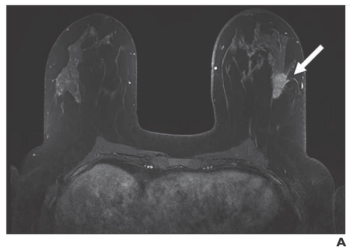

Suspicious lesions that develop during neoadjuvant therapy are uncommon, and they are highly unlikely to be malignant.